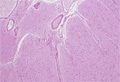

- ★(8)Glioma(Astrocytoma)

Macroscopic findings: Relatively indistinct tumor mass was detected in the lateral lobe around the left lateral ventricle (red circle).